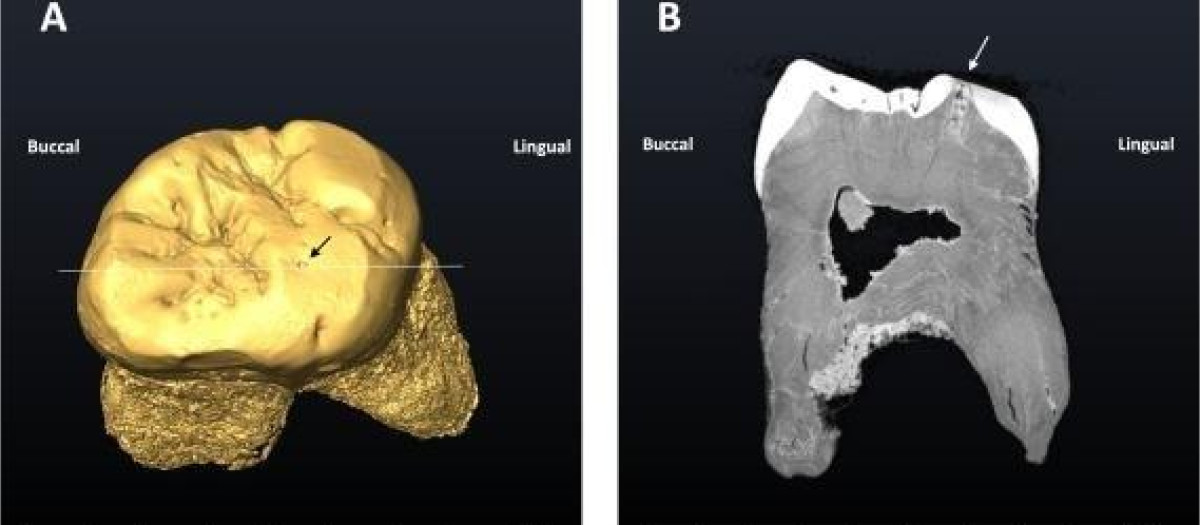

Para llevar a cabo el análisis, los científicos aplicaron métodos no destructivos como la microscopía electrónica de barrido ambiental, que permitió examinar con gran detalle la superficie del diente y observar los efectos del proceso carioso. Asimismo, se empleó tomografía axial computarizada, lo que posibilitó obtener imágenes en tres dimensiones del interior del molar, verificar la extensión de la descalcificación y confirmar la profundidad de la lesión sin dañar el fósil.

El individuo en cuestión, conocido como 'adulto 6' de El Sidrón, presentaba un notable deterioro de la dentición. La investigación indica que la fisura provocada por el uso intensivo de los dientes fue colonizada progresivamente por bacterias, desarrollando una caries incipiente con forma de canal y una longitud de 2,6 milímetros.

«Todo apunta a que el uso intenso de la dentición pudo provocar una fisura que, poco a poco, fue colonizada por bacterias que profundizaron en el esmalte y la dentina hasta desarrollar la caries: una lesión en forma de canal de 2,6 mm de longitud», explicó Almudena Estalrrich, investigadora del MNCN-CSIC.